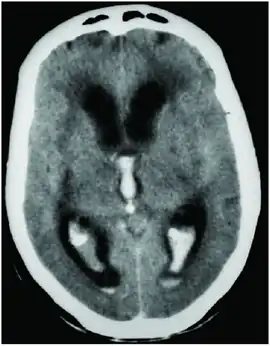

| CT scan showing spontaneous intracerebral hemorrhage with bleeding in the third and both lateral ventricles and hydrocephalus[1] | |

Prognosis is very poor when IVH results from intracerebral hemorrhage related to high blood pressure and is even worse when hydrocephalus follows.[1] It can result in dangerous increases in ICP and can cause potentially fatal brain herniation.[1] Even independently, IVH can cause morbidity and mortality. First, intraventricular blood can lead to a clot in the CSF conduits blocking its flow and leading to obstructive hydrocephalus which may quickly result in increased intracranial pressure and death.[15] Second, the breakdown products from the blood clot may generate an inflammatory response that damages the arachnoid granulations, inhibiting the regular reabsorption of CSF and resulting in permanent communicating hydrocephalus.[2][15]